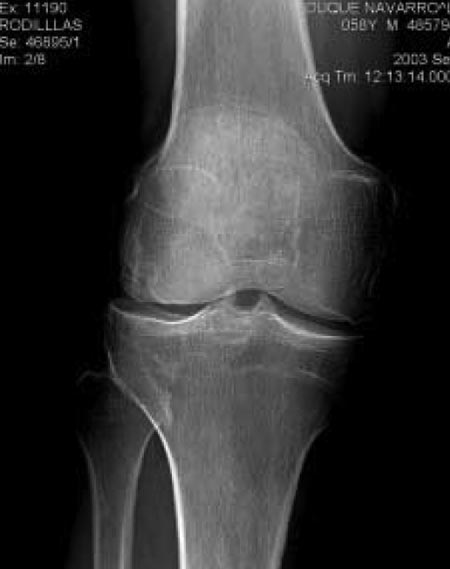

Se pudo observar que la proyección de Rosenberg en comparación con la proyección AP tiene mayor capacidad de detectar la disminución del espacio articular cuanto mayor es éste (más espacio remanente), es decir la proyección de Rosenberg, a diferencia de la proyección AP convencional es capaz de detectar estadios de artrosis incipiente (Gráfico 1). A medida que la enfermedad progresa y existe una disminución considerable en la altura del espacio articular, ambas proyecciones tienen un rendimiento similar. (Fig. 2A y 2B).

Figura 2A: Proyección radiográfica AP convencional de un paciente con síntomas de gonartrosis. Los espacios articulares se ven conservados.

Figura 2B: Proyección de Rosenberg del mismo paciente, una importante disminución del espacio tibiofemoral lateral.